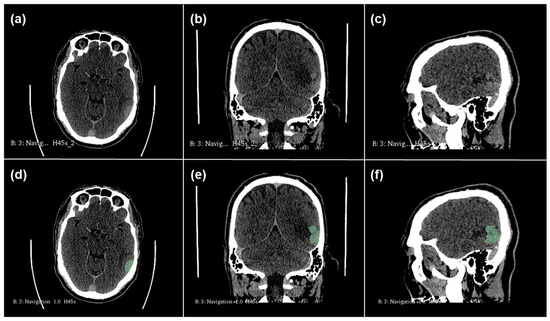

2.1. Radiomics